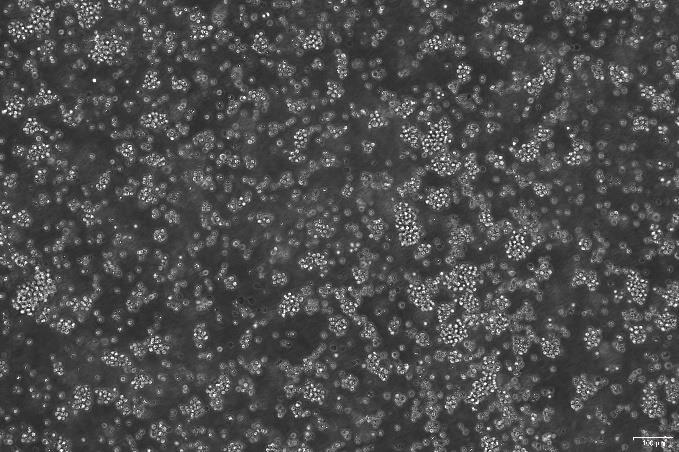

OriCell®TMD8 人弥漫性大B淋巴瘤细胞系

人弥漫性大B淋巴瘤细胞系(TMD8)来源于一名B淋巴细胞瘤患者,该细胞表达HES1 mRNA,表达Notch蛋白;细胞生长会受到γ-分泌酶的影响。

悬浮生长;淋巴母细胞样 |